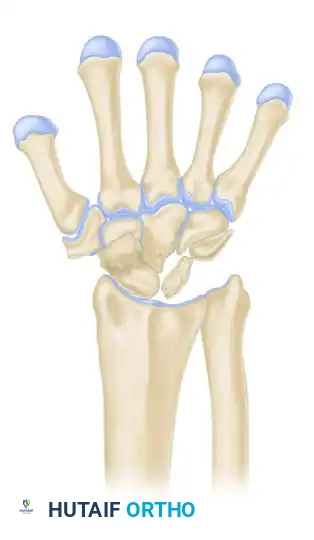

LICHTMAN CLASSIFICATION OF KIENBÖCK DISEASE

The staging classification proposed by Lichtman et al. is the universally accepted framework for guiding surgical decision-making. The natural history, if left untreated, progresses from sclerosis to fragmentation, carpal collapse, and ultimately pancarpal arthritis.

Stage IV

- Description: Advanced degeneration. Secondary osteoarthritic changes extend to the adjacent intercarpal and radiocarpal joints.

- Treatment: Salvage procedures including wrist arthrodesis (total wrist fusion), proximal row carpectomy, or limited intercarpal fusions.